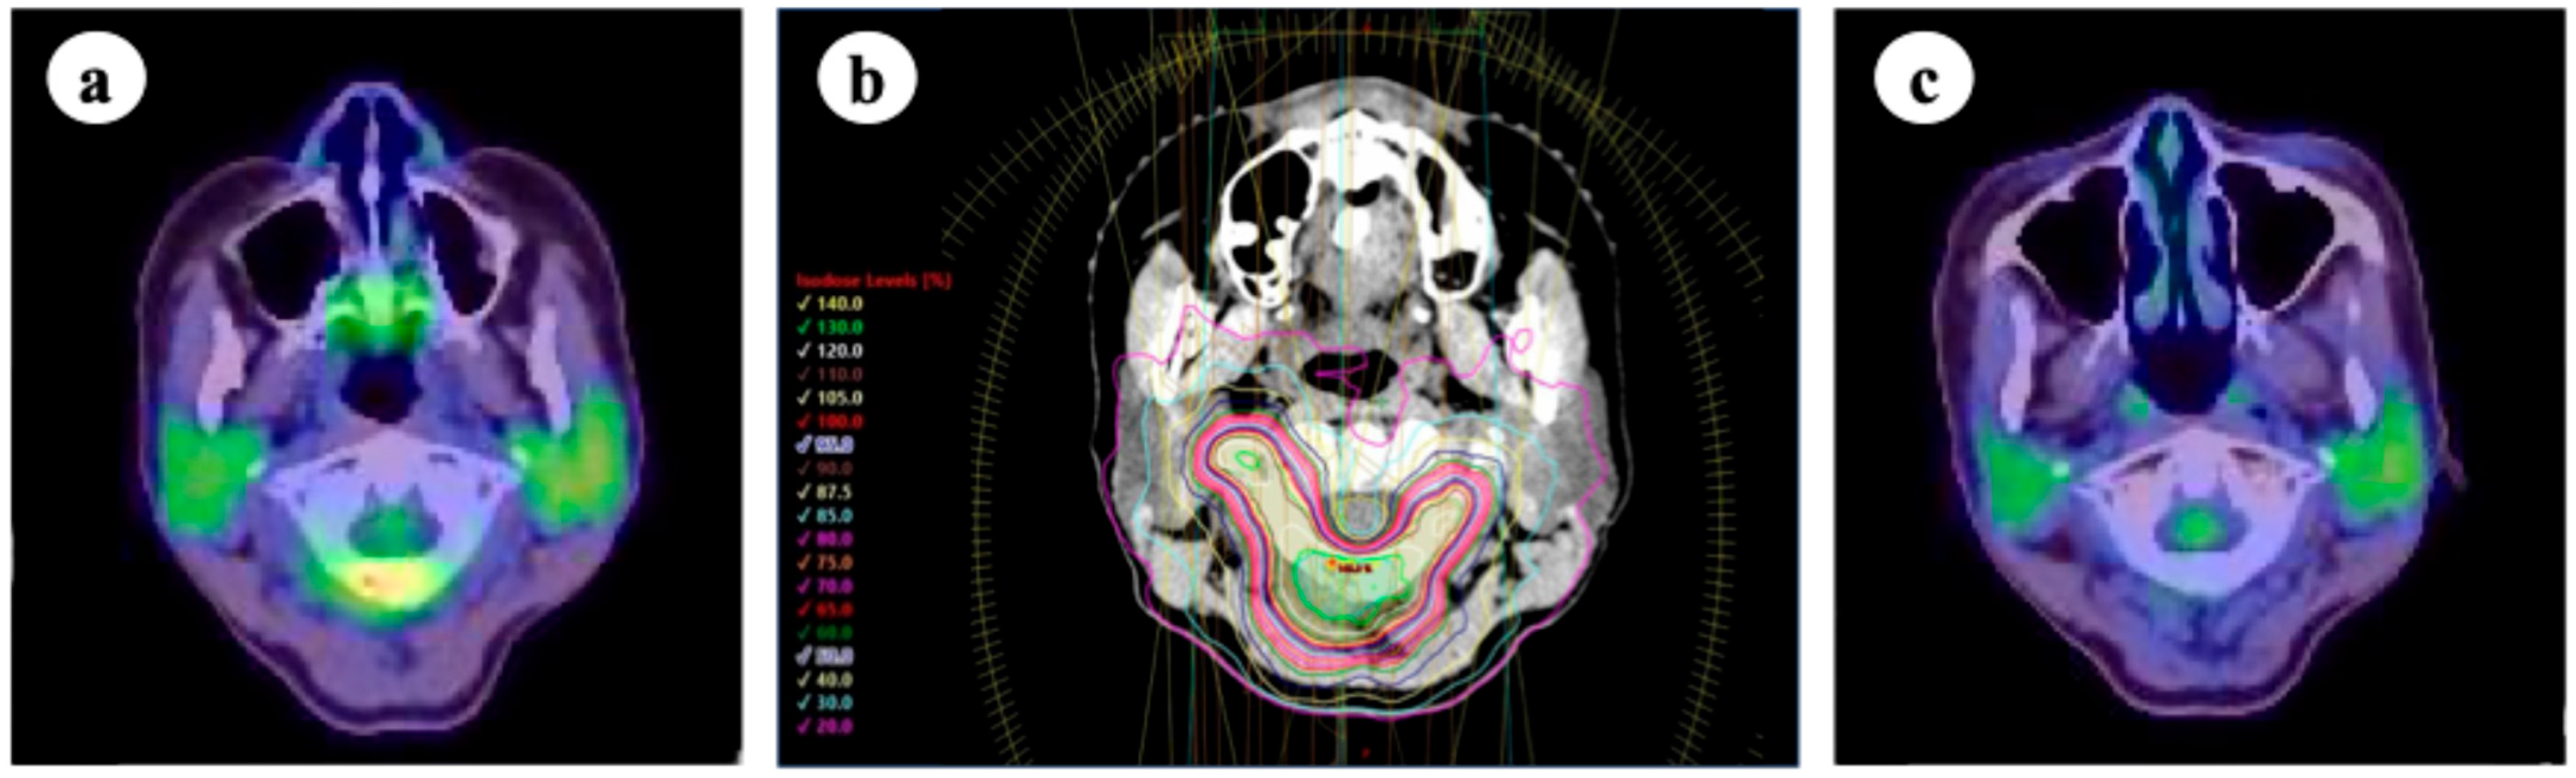

The efficacy of local therapy for oligometastatic lung cancer in improving prognosis and local control rates has been demonstrated in various clinical trials. In a randomized phase II trial conducted by Gomez et al. to evaluate the efficacy of local therapy for oligometastatic NSCLC, bone oligometastases were observed in 10 of 49 cases [3]. However, most patients receive conventional radiotherapy (30–45 Gy in 10–15 fractions). Currently, SBRT is often considered for the treatment of bone oligometastases. The SC.24 trial [72] was a randomized phase II/III comparative trial evaluating the efficacy of SBRT (24 Gy in two fractions) versus conventional radiotherapy (20 Gy in five fractions) in patients with painful spinal metastases, with lung cancer cases comprising 61 out of the 229 enrolled patients (26.6%). The primary endpoint, the complete pain response rate at 3 months, was significantly higher in the SBRT group (35% vs. 14%, p < 0.001), confirming its superiority. Subsequent long-term analyses demonstrated that the 2-year local control rate was significantly higher in the SBRT group than conventional radiotherapy (85% vs. 64%, p < 0.001), with no significant differences in adverse events between the groups [73]. The potential benefit of SBRT for bone oligometastases has also been highlighted in a multicenter phase III trial led by Zelefsky et al., which included 11 patients with lung cancer out of 117 (9.4%) [74]. A median follow-up period of 52 months indicated favorable long-term outcomes in this population. These results suggest favorable efficacy and safety of SBRT in the treatment of locally controlled bone oligometastases. Currently, there is no consensus regarding the optimal SBRT dose fractionation for local bone oligometastatic control. Zelefsky et al. investigated the local efficacy of two SBRT regimens for bone oligometastases: 24 Gy in a single fraction and 27 Gy in three fractions. Their findings showed a significantly higher local control rate in the single-fraction arm, with local recurrence rates at 2 and 3 years of 2.7% and 5.8%, respectively, compared with 9.1% and 22% in the three-fraction arm (p = 0.0048). Regarding spine SBRT, a meta-analysis by Soltys et al. showed that radiation doses of 18–24 Gy in a single fraction, 24 Gy in two fractions, 30 Gy in three fractions, 33 Gy in four fractions, and 35 Gy in five fractions all achieved 2-year local control rates > 80%, serving as a valuable reference for clinical practice [75]. A survey conducted by the Subcommittee of the High-Precision External Beam Radiotherapy Group of the Japanese Society for Radiation Oncology showed that 30–35 Gy in five fractions and 24 Gy in two fractions, prescribed to 95% of the PTV, are commonly used in clinical practice in Japan [65]. An example of dose distribution of SBRT for an atlas vertebra is shown in Figure 3. Regarding non-spine SBRT, a recent systematic review and meta-analysis conducted under the auspices of the International Stereotactic Radiosurgery Society reported favorable outcomes, with pooled local control rates of 95% at 1 year and 94% at 2 years [76]. In this report, the expert consensus recommended dose fractionation schedules of 18–24 Gy in a single fraction, 27–30 Gy in three fractions, and 30–35 Gy in five fractions. Although the panel supported dose escalation beyond 35 Gy up to 50 Gy in five fractions, the optimal maximum dose remains unclear owing to limited clinical data. Within these ranges, a higher dose was considered beneficial for improving local control; however, the prescribed dose should be carefully adjusted based on factors such as the proximity of organs at risk, prior radiation history, and anatomical considerations. Evidence specifically focusing on bone oligometastases from lung cancer remains limited, and further investigation is warranted to determine the optimal SBRT strategy in this subset. In this context, the results of the ongoing multicenter phase III trial (STEREO-OS trial), which evaluates the efficacy of SBRT for bone oligometastases in various solid tumors including NSCLC, may provide valuable clinical insights in the future [77].

Figure 3.

(a) 18-fluoro-deoxyglucose positron emission tomography/computed tomography (FDG-PET/CT) before stereotactic body radiotherapy (SBRT); (b) SBRT targeting the atlas (24 Gy in two fractions, prescribed to 95% of the planning target volume [PTV] and 70% isodose line); (c) FDG-PET/CT 1 year after SBRT. The lesion remained controlled without significant adverse events.